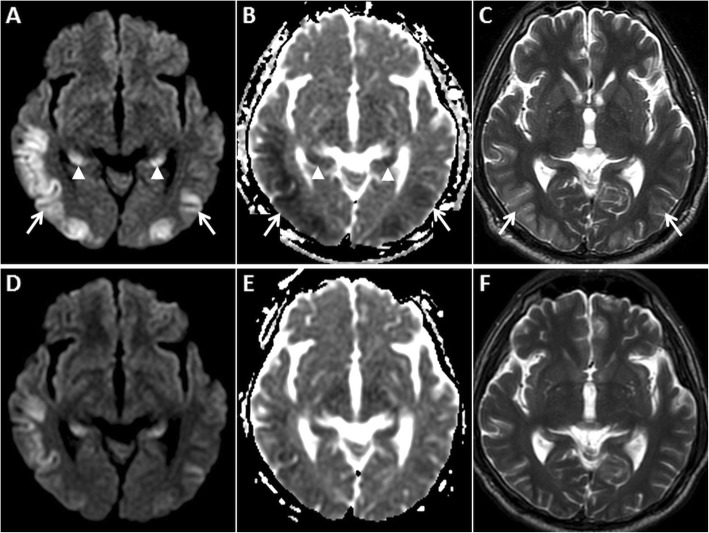

Fig 6.

MRI of the brain in a 26-year-old female patient brought unconscious following valproate overdose. Symmetric GRD is seen in the cingulate gyri (arrows) on axial DWI (a) and ADC image (b). GRD is also seen in the insular cortices (arrows) on axial DWI (d) and ADC image (e). Coronal FLAIR images (c, f) reveal hyperintense cortical swelling in these regions, along with similar signal changes in bilateral mesial temporal lobes. Laboratory tests confirmed the diagnosis of hyperammonaemia

Fig. 7.

Pre and post-contrast MRI of the brain in a 70-year-old male patient who presented with altered mental status and discharging left ear. Localised GRD is seen in the posterior part of the left inferior temporal gyrus (arrows) on axial DWI (a) and ADC image (b) along with surrounding vasogenic oedema on axial T2W image (c). There are tiny haemorrhages (dashed arrow) in this lesion on axial GRE image (d) and subtle gyriform enhancement (arrowhead) on post-contrast axial T1W image (e). Coronal reconstruction of subsequent high-resolution CT of the left temporal bone (f) reveals extensive left otomastoiditis with a large bony defect in the left tegmen tympani (stepped arrow). Imaging findings are in keeping with complicated left otomastoiditis leading to cerebritis